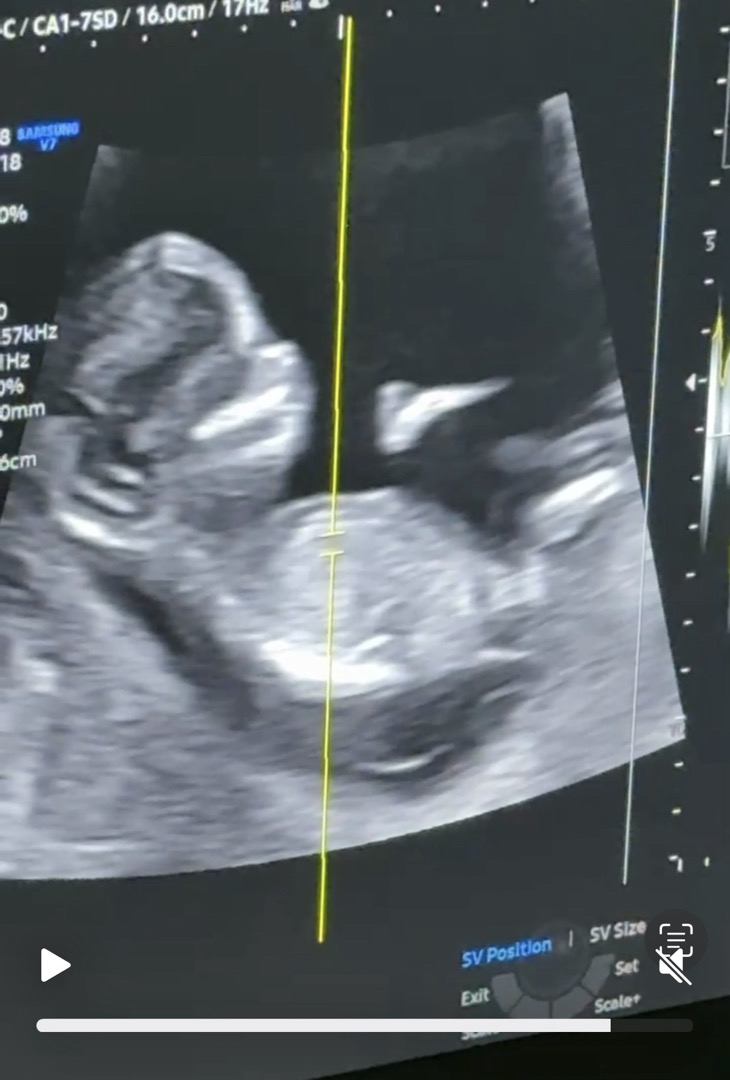

아기엎드린것만 보다 옆모습 처음으로봣어요 ㅠㅠ

처음본 울아기 옆모습이라 자꾸보고잇어욬ㅋㅋㅋ 딸인거같나요?!!! 참견부탁드립니다🥹❤️

돌기가 솟아있어요. 아들 각도 같아요.